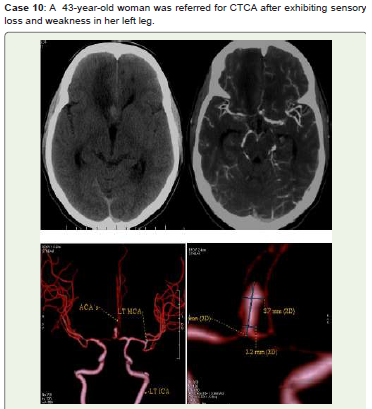

Figure 10:Right frontal lobe infarct is seen on CT Axial non-contrast (A),

MIP (B), and 3D-VR images (C, D) show a large ACOM saccular aneurysm

with a neck diameter of 2.2 mm and a high ellipticity index, squeezing the

right ACA’s A2 segment and generating a mass effect. He was scheduled

for immediate endovascular treatment but did not show up for the follow-up.